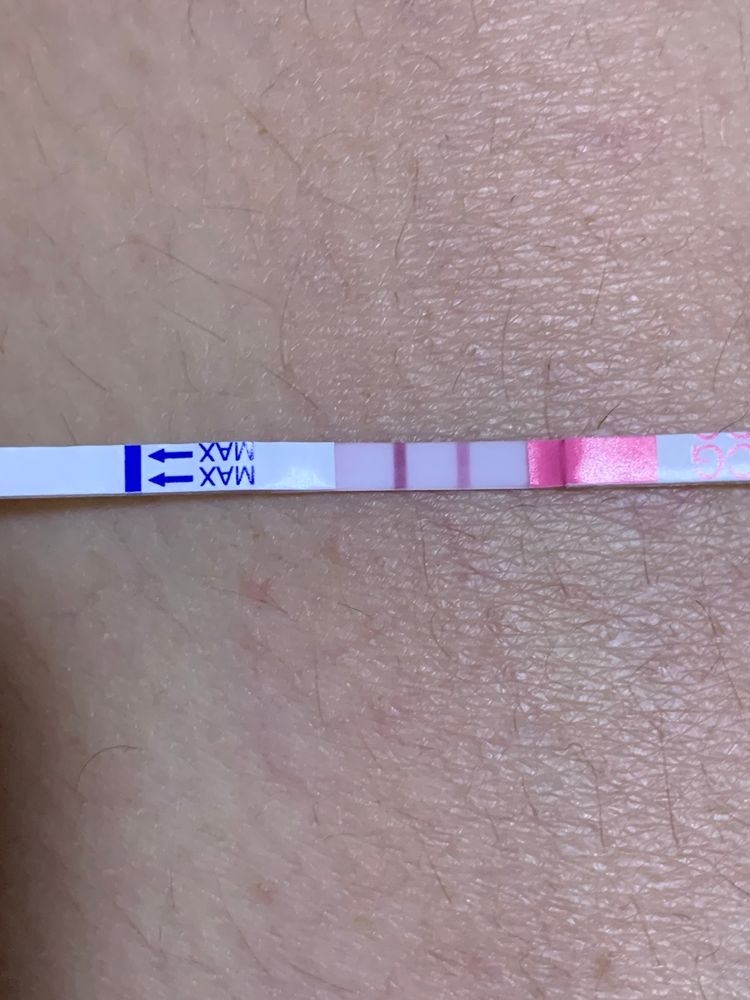

Девочки , плохая очень тема, но хочется успокоится и получить от вас информацию. Может ли замершая беременнось, выкидыш пройти незаметно. Без болей, кровотечения... Было последнее узи на 6й недели. Два деформированных плодных яйца(не знаю почему деформированные). Далось мне сдать тесты три разные, фото прикрепила. Последний хгч был 29октября 152000.